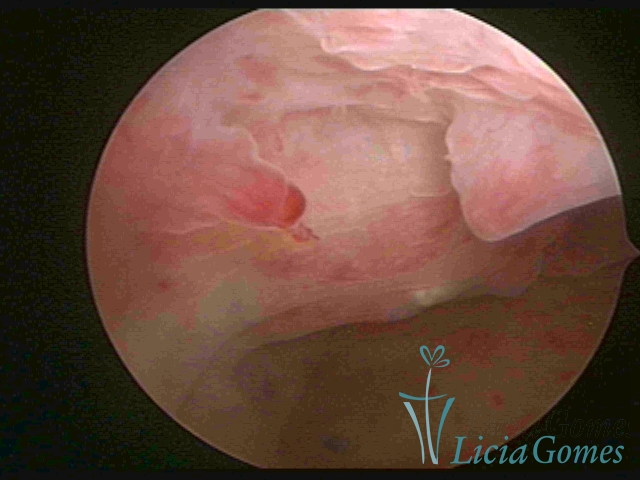

A hipertrofia polipoide é visualizada quando o crescimento endometrial é mais pronunciado, e como o espaço da cavidade uterina é limitado, forma dobras ou sulcos, simulando lesões pseudo polipoides ou polipoides.

A Hiperplasia Complexa tem um aspecto pseudo polipoide, lembrando tecido cerebroide ou com reação deciduoide. A vascularização superficial é mais evidente e com vasos em formatos de saca-rolha ou espirais.

A Hiperplasia atipia e o aspecto histeroscópico são semelhantes à da hipertrofia complexa, visualizando também a vascularização com atipias. Com o aumento do calibre dos vasos superficiais, pode ser encontrado também tecido em necrose.